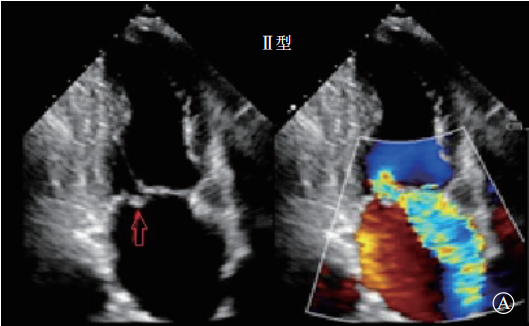

Ⅱ型:瓣叶活动过度的瓣膜功能失调(瓣膜脱垂,图3)。定义为一个或多个瓣叶活动度增加,瓣叶的游离缘在瓣叶关闭时超过了瓣膜口关闭时的平面,血流动力学结果提示为瓣膜反流,由于腱索断裂或延长,或者乳头肌断裂导致。

图3 Ⅱ型,过度瓣膜运动 A. 后叶过度运动,导致后叶脱垂,重度二尖瓣反流;B. 前叶过度运动,导致前叶脱垂,重度二尖瓣反流